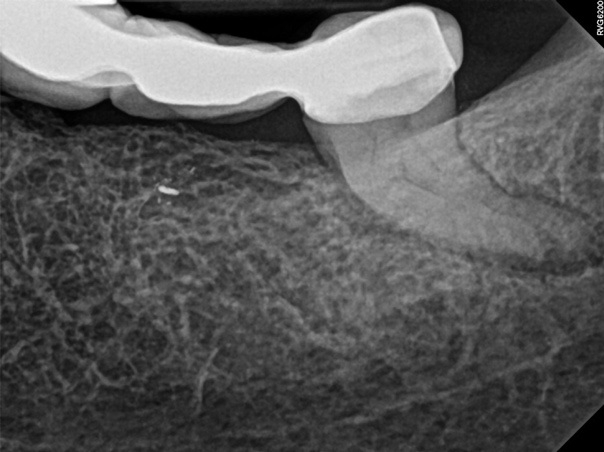

Figure 6 through Figure 8 demonstrate that, 5 months after the procedure, complete healing had occurred, notably on the distal, where the probing had resolved to 2 mm. The patient then had a crown placed by her general dentist. Given her positive experience with the technology, she was eager to return as needed for continued follow-up.

Fig 6. Case 1: CBCT showed a large lateral canal within the palatal root (Fig 3). There was a small preparation space, which was efficiently obturated (Fig 4). A small pinpoint of sealer in the middle of the palatal root indicated that the palatal lateral canal had been addressed (Fig 5). After 5 months, CBCT demonstrated complete healing (Fig 6), notably on the distal, where probing had resolved to 2 mm. Radiographic images were taken immediately postoperatively (Fig 7) and 5 months postoperatively (Fig 8).

Figure 6

Fig 7. Case 1: CBCT showed a large lateral canal within the palatal root (Fig 3). There was a small preparation space, which was efficiently obturated (Fig 4). A small pinpoint of sealer in the middle of the palatal root indicated that the palatal lateral canal had been addressed (Fig 5). After 5 months, CBCT demonstrated complete healing (Fig 6), notably on the distal, where probing had resolved to 2 mm. Radiographic images were taken immediately postoperatively (Fig 7) and 5 months postoperatively (Fig 8).

Figure 7

Fig 8. Case 1: CBCT showed a large lateral canal within the palatal root (Fig 3). There was a small preparation space, which was efficiently obturated (Fig 4). A small pinpoint of sealer in the middle of the palatal root indicated that the palatal lateral canal had been addressed (Fig 5). After 5 months, CBCT demonstrated complete healing (Fig 6), notably on the distal, where probing had resolved to 2 mm. Radiographic images were taken immediately postoperatively (Fig 7) and 5 months postoperatively (Fig 8).

Figure 8